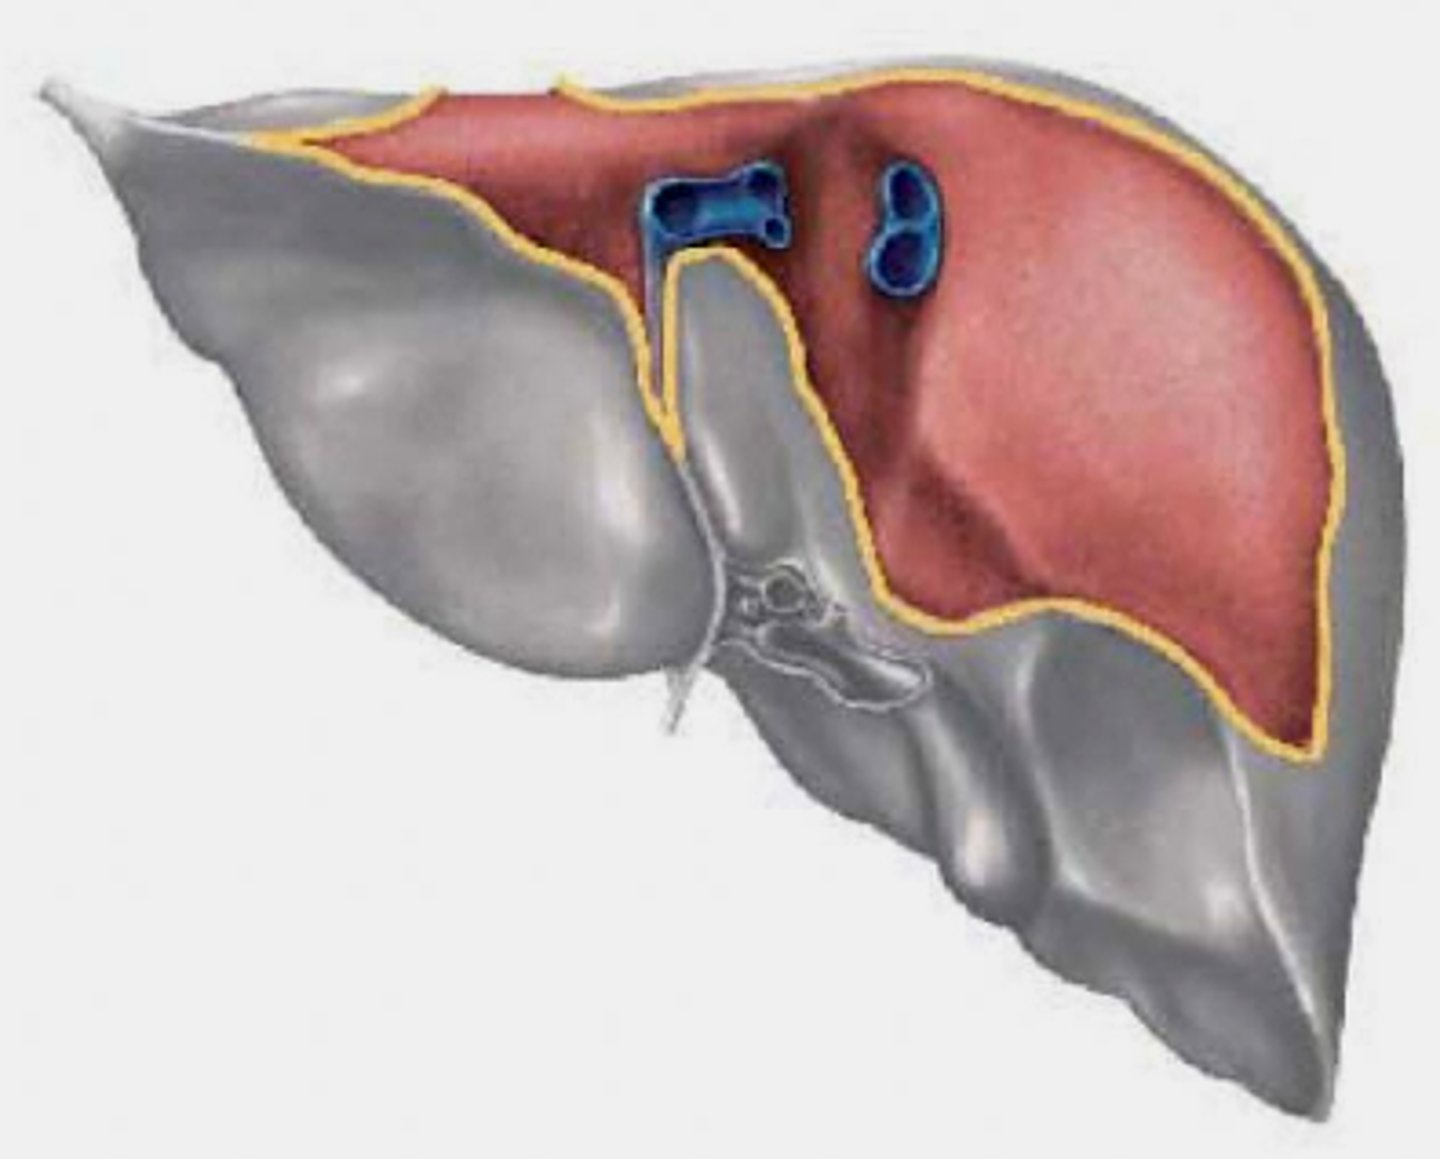

Identify the lobes of the inferior portion of the liver

What is the porta hepatis?

Hilum of liver (transverse hepatic fissure) - contains components of hepatic artery, hepatic ducts and portal vein.

region of structures entering and exiting the liver

Identify the anterior lobes of the liver

Identify impressions on the inferior portion of the liver

Note that organs in direct contact with liver can spread cancer directly to the liver